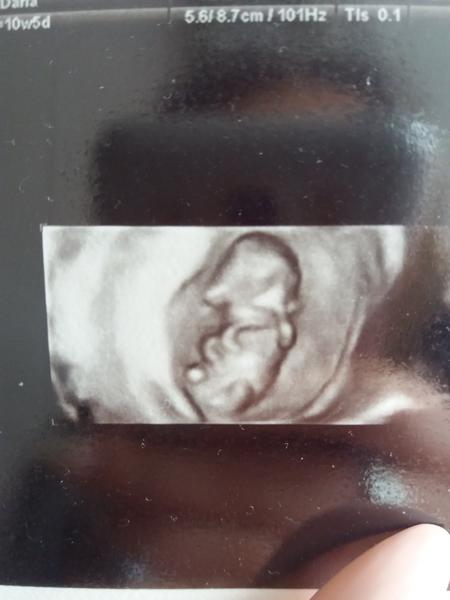

@archanjel007 ďakujem veľmi sa tešíme že takto rastie.

@archanjel007 ďakujem ti veľmi pekne celá rodina pevne veríme že tento raz to dotiahneme až do šťastného konca.